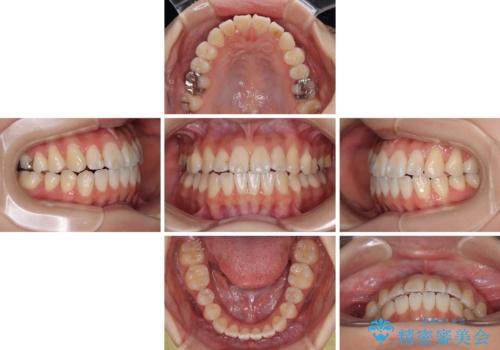

舌の突出癖が原因 インビザライン矯正による開咬改善

- 患者様

- 20代女性

- 矯正装置

- インビザライン

- 前歯の開咬を気にして来院された患者様です。

開咬の治療は、前歯を閉じるように動かすとともに、上下臼歯を圧下(骨内にめり込ませる)させることで進めて行きます。

インビザラインは臼歯の圧下を効果的に行えるため、インビザラインを用いて矯正治療を行うこととしました。